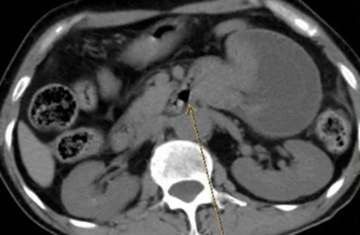

小肠

梗阻是犬的一种

急腹症

,常因小肠肠腔发生机械性阻塞或小肠正常位置发生不可逆变化,如套叠、嵌闭、扭转等。小肠梗阻除造成肠管不通外还同时伴有局部血液循环障碍。